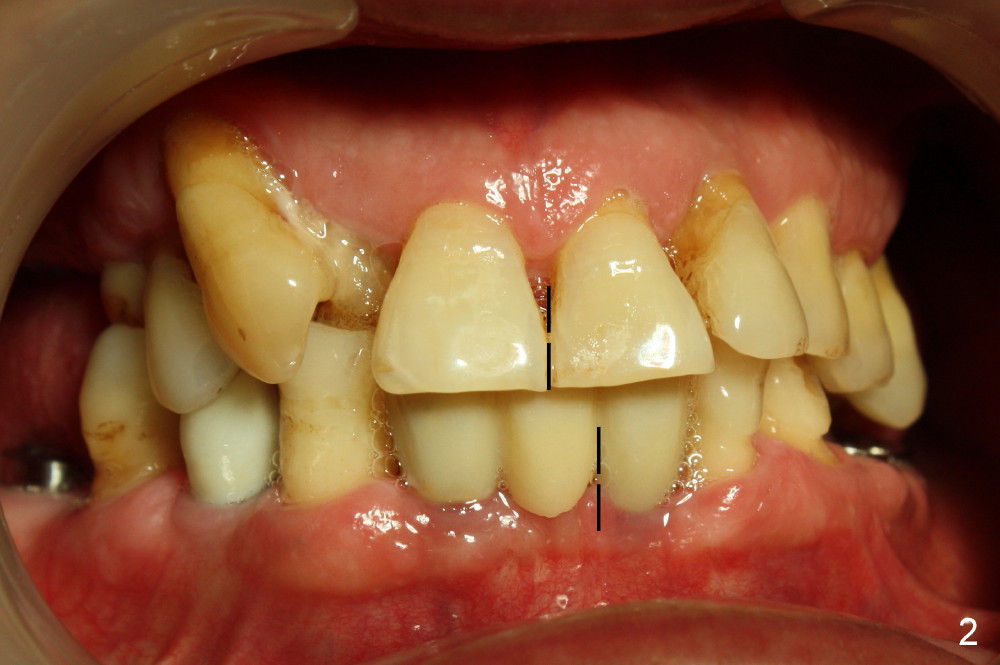

Clinical exam reveals that the upper midline appears to be deviated to the right (Fig.2), while the left canine relationship is Class II (Fig.3). Therefore, the upper anterior teeth (#9-12) will be moved distally orthodontically. When the tooth #13 is extracted, the immediate implant should be placed more distal than usual. This implant, once osteointegrated, will be used an anchorage for distaliztion of the teeth mesial to it.